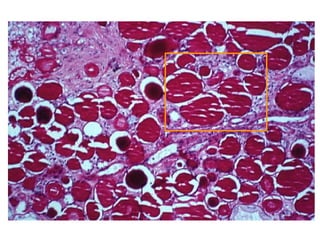

URATE NEPHROPATHY

• Precipitation of Uric Acid Crystals in

the TUBULES, especially in a LOWER

than usual PH situation (mini-TOPHUS)

H & E alcohol fixed POLARIZED LIGHT MICROSCOPY

• Three forms:

– Acute uric acid nephropathy … chemotherapy

related

– Chronic urate nephropathy … gouty, tophi

– Nephrolithiasis … stones

URATE NEPHROPATHY • Precipitationof Uric Acid Crystals in the TUBULES, especially in a LOWER than usual PH situation (mini-TOPHUS) H & E alcohol fixed POLARIZED LIGHT MICROSCOPY

• Three forms: –Acute uric acid nephropathy … chemotherapy related – Chronic urate nephropathy … gouty, tophi – Nephrolithiasis … stones